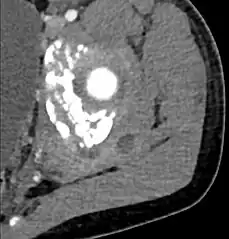

CT with IV contrast showing enlargement and heterogeneous hypodensity in the right pectoralis major muscle. A focal abscess collection with gas within it is present medially. There are enlarged axillary lymph nodes and some extension into the right hemithorax. Note the soft tissue and phlegmon surrounding the right internal mammary artery and vein. The patient was HIV+ and the pyomyositis is believed to be due to direct inoculation of the muscle related to parenteral drug abuse. The patient admitted to being a "pocket shooter"

| Diagnostic method | Diagnostic method used for PM includes ultrasound, CT scan and MRI. Ultrasound can be helpful in showing muscular heterogeneity or a purulent collection but it is not useful during the first stage of the disease. CT scan can confirm the diagnosis before abscesses occur with enlargement of the involved muscles and hypodensity when abscess is present, terogenous attenuation and fluid collection with rim enhancement can be found. MRI is useful to assess PM and determine its localization and extension |